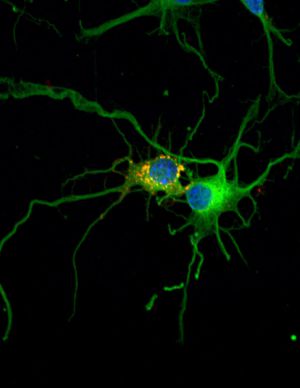

![]() |

| Dos Neuronas |